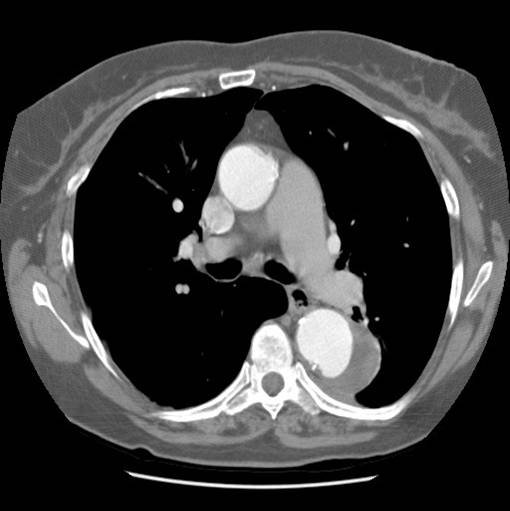

| Figure 1: Contrast-enhanced chest CT scan demonstrating 6-cm aneurysm of the mid-descending thoracic aorta |

There were no remarkable findings on physical exam. A chest x-ray revealed a widened mediastinal silhouette, and a high-resolution contrast-enhanced computed tomography (CT) scan was performed using 3mm slices, which demonstrated an isolated 6-cm aneurysm in the mid-portion of the descending thoracic aorta (DTA) (Figure 1). Three dimensional reconstructions were performed from the chest CT scan (Figure 2).